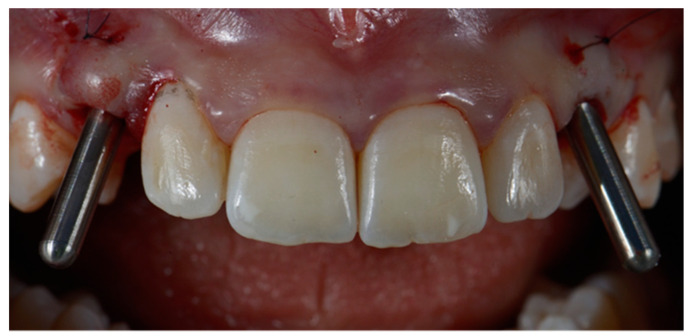

One week after planning, the flap was elevated with a papilla preservation technique, and guided implant placement was performed. Once designed, the flap was disepitelized using a diamond bur. Then, the flap was elevated to expose bone. Soft tissues were reflected with a roll-flap with the aim of increasing the volume on the buccal side. Implant (Sweden & Martina, Padua, Italy) was then inserted, and a digital impression with implant-level PEEK scan bodies was made. The healing abutments were screwed and a 6.0 suture was positioned (monofilament-polyglecaprone suture, Surgiclryl-Monofast, ®SMI-Belgium) to stabilize the soft tissues (Figure 3 and Figure 4).

Figure 3.

Surgical guide template.

Figure 4.

Implants insertion with positioning pins.